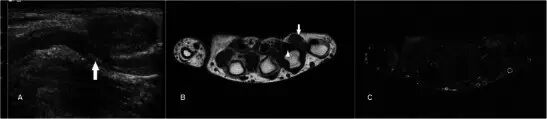

腱鞘囊肿Ganglion cyst 腱鞘囊肿是手部和手腕区域中最常见的肿块[2]。他们往往发生在年轻的成年人,女性发病更加频繁。它们被认为代表由慢性刺激引起的结缔组织的退化[3]。最常见的位置是在手腕的舟月关节背部。较不典型的部位包括手腕的掌侧从桡骨-舟骨( radio-scaphoid )或舟骨-大多角骨(scapho-trapezial)关节,在相对于掌指关节,以屈肌腱和远端指间关节[4]。MR显示了流体信号的良好外切的单个或多腔的损伤,但是信号可以根据蛋白质含量的量而变化(图1)。可以看到囊的轻度边缘增强,但是通常没有内部内容物的增强。鉴别诊断包括滑膜囊肿和其他囊性病变,例如表皮囊肿。

图1.24岁的女性腱鞘囊肿,呈现一个缓慢成长,坚定,无痛的手肿大约6个月。 (a)T1w序列显示在均匀低信号的大鱼际肌组织内的平滑、良好边缘病变。 (b)T2w-FS序列上的病变是高信号的。 没有看到侵入相邻结构。 (c)有最小的边缘增强,没有显着的内部增强(箭头)